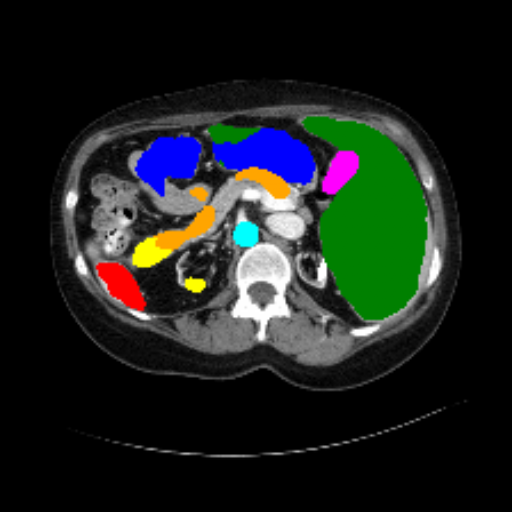

Figure 3 presents a qualitative comparison of segmentation performance on examples from the Synapse, BTCV, ACDC, and ISIC17 datasets. The first two examples (from Synapse) highlight variations in segmentation performance among U-Net, TransUnet, Mamba-Unet, and Swin-Unet. While Swin-Unet performs well in the first example, its performance decreases in the second example, particularly in segmenting the organ highlighted in blue. Additionally, it misclassifies background regions as the class highlighted in orange. In contrast, our approach demonstrates high robustness in segmenting all classes accurately and aligning well with the ground truth masks.

Refer to caption Refer to caption Refer to caption Refer to caption Refer to caption Refer to caption Refer to caption

Slice GT Unet TransUnet Mamba-Unet Swin-UMamba MambaCAFU-V1

Figure 3: Visual comparison of segmentation examples from Synapse (first two examples), BTCV (3-4 examples), ACDC (5th example) and ISIC17 (last example). Columns: input slice, ground truth, Unet, TransUnet, Mamba-Unet, Swin-UMamba, and MambaCAFU-V1.